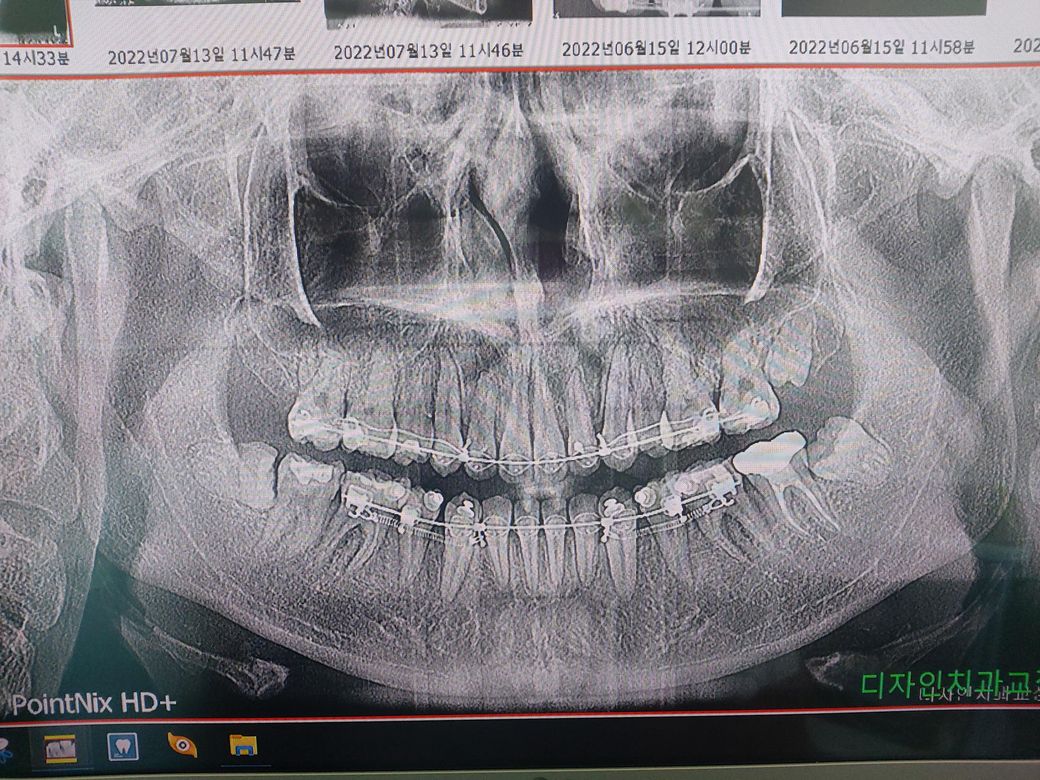

사랑니가 3개정도 있는데요 아래에 2개 위에 1개 이렇게 있다고 하는데.. 위에는 모르겠고 아래거는 교정때문에 되도록이면 빼라고 하던데요. 궁금해서 허락받고 사진 찍어왔습니다. 아래쪽 사랑니 2개 발치 많이 힘들까요...? 제가 치과를 진짜 싫어하고 가는걸 힘들어하는데 사랑니 전문 치과가 좀 먼 곳으라 대중교통을 타고 가야해서 통증 심하면 어떡할지 걱정도 되구요 ㅠㅜㅜ 엑스레이 사진 한번 봐주실수 있나요

환자 분 기준으로 오른쪽 아래 부위는 조금 시간이 걸릴 수 있어 보입니다. 다만 나머지 왼쪽 위, 아래의 치아는 사랑니 발치에 크게 시간이 걸리지 않을 것으로 보이며 당일 날 같이 발치도 가능해 보입니다. 오른쪽 아래도 시간이 걸릴 뿐 신경과 근접하지 않기 때문에 부작용이나 후유증 없이 발치 가능할 것으로 보입니다.

크게 어려운 난이도는 아니신거 같습니다. 환자분이 입만 잘 벌리신다면 크게 어려운 발치는 아니세요.

난이도를 굳이 매기자면 왼쪽위<왼쪽아래<오른쪽 아래 순으로 발치 난이도가 높습니다.